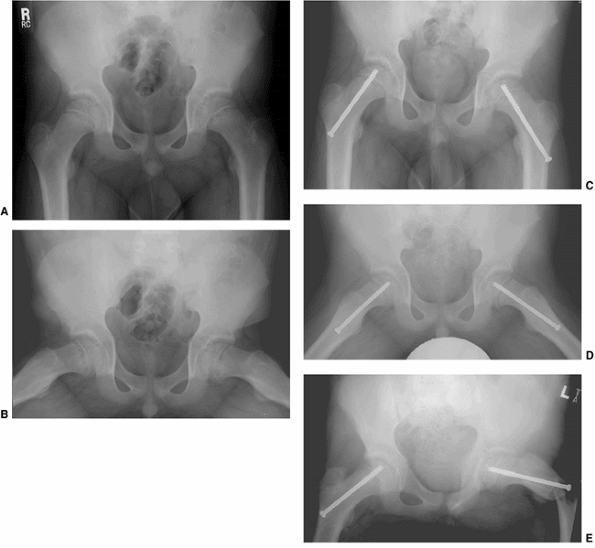

![]() |

Figure 26.6 Proper screw locations in slips of varying severity in three different cases: (A, B), (C, D), and (E, F).

In all three cases, the screws enter the anterior femoral neck, are perpendicular to the physis, and are located in the center of the femoral head. The starting point is more proximal and the screw is angled progressively more posteriorly as the magnitude of slip progresses from least (A, B) to most (E, F) severe. |

Figure 26.8

A 12-year-old boy presented with bilateral stable slipped capital femoral epiphysis (SCFE). Anteroposterior and lateral radiographs demonstrate mild bilateral SCFE (A, B). Postoperative radiographs demonstrate that both screws were inserted through the lateral cortex at or distal to the lesser trochanter (C, D). Six weeks postoperatively the boy had acute onset of pain while playing baseball, due to a left subtrochanteric fracture (E). Proximal femoral fractures occur most commonly when hardware enters the lateral cortex of the femur at or distal to the lesser trochanter, and may also occur through unused drill holes at this level. Because of the posterior direction of slip, an anterior femoral neck starting point would have been feasible in this case, and preferable both for biomechanical reasons and the lower risk of fracture associated with an anterior starting point. |